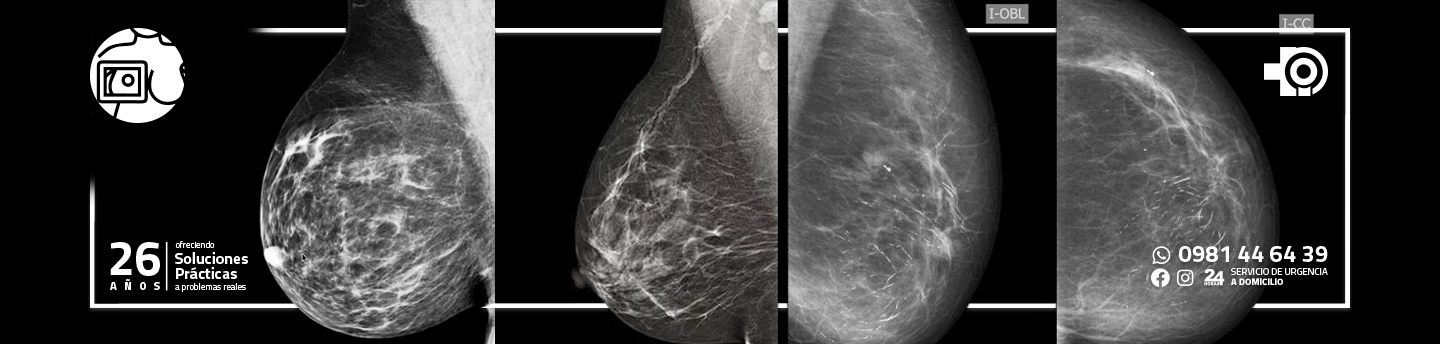

MAMOGRAFÍA

La mamografía digital proporciona exploraciones muy precisas y rápidas para el radiólogo y brinda a los pacientes la más alta calidad de atención en la prevención y detección temprana del cáncer de mama.

La mamografía digital utiliza computadoras y detectores digitales especialmente diseñados para producir una imagen que se puede mostrar en un monitor de computadora de alta resolución, y transmitir y almacenar como los archivos de computadora. La tecnología permite a los radiólogos ver las imágenes de rayos x en cuestión de segundos. Pueden ajustar el brillo, cambiar el contraste y ampliar áreas específicas para ayudar a detectar pequeñas calcificaciones, masas y otros cambios que pueden ser signos tempranos de cáncer. La habilidad de manipular imágenes es uno de los beneficios de la tecnología digital.